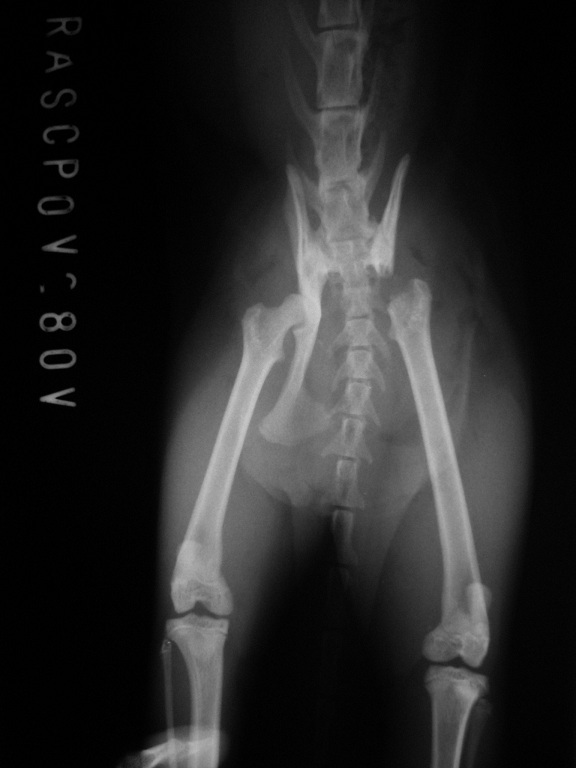

主題: 因排便困難而做半邊骨盆移除手術與術後回診的艾咪 申請者姓名: 臺北市支持流浪貓絕育計劃協會 花色: 申請日期: 2016-09-16 18:11:37 申請者部落格: 申請者臉書網址: 所在縣市/合作醫院: 台北市/其他院所醫助專案(醫院請先MAIL溝通) 治療費用: 66200元 需求人數: 69人 已結案 (2022-05-13 15:22:04) 報名人員: 艾妮(已付款)、tigercat(已付款)、Honey(已付款)、Cian Huei Yang(已付款)、劉宗鑫 x3(已付款)、蔡翔恬 x2(已付款)、Ting(已付款)、Lingying Jennifer Chou(已付款)、李坤財(已付款)、廖乙霖、Michelle Kuan(已付款)、Mandy Chen(已付款)、Tzu Ning Kuo(已付款)、Juphy Chiang(已付款)、Ying-chen Chiu x2(已付款)、Juen-Nien Lin x2(已付款)、Chia-chun Hsieh(已付款)、楊閔華(已付款)、leelpr(已付款)、Kristy Lee(已付款)、Nomar(已付款)、bootscat(已付款)、Ginger x2、Kira Chang(已付款)、Amily Hung(已付款)、大里阿維(已付款)、Love4animals、Ruth Wang(已付款)、Amberger(已付款)、王香香(已付款)、Q咩(已付款)、Ginger x2(已付款)、Peggy Wu x2(已付款)、郭庭甄(已付款)、櫻花妹(已付款)、Ginger、Cloud Lee、Cloud Lee(已付款)、Jessy(已付款)、YH秀(已付款)、比比(已付款)、香香(已付款)、Moni(已付款)、Kim Lin(已付款)、薇薇安(已付款)、我愛摺耳貓(已付款)、Hazel Wang(已付款)、billcat(已付款)、Selene Tsai(已付款)、aqwed(已付款)、emmahsu(已付款)、fang7880(已付款)、阿敏(已付款)、楊育昇(已付款)、Rona Chen(已付款)、Mia Chao(已付款)、Monica Wang(已付款)、ERic YU(已付款)、Qness Chen(已付款)、888(已付款)、Anita(已付款)、Bella Hung(已付款)、小虎的媽(已付款)、鄭閔文(已付款)、vivian(已付款)、julie lee(已付款)、鄭筠巧(已付款)、 候補人員: 動物病情說明: 艾咪很小的時候就在街上流浪,

但不幸遭遇車禍事故導致骨盆左右腸骨骨折,

使得骨盆下方的最狹窄處只有4mm,

雖然在經過醫生手術後將其拓寬為8mm。

但因為貓咪正常排便需要10mm以上的骨盆寬度,

5/26術前回診

艾咪兩天後要進行骨盆移除手術,

因此先至醫院做詳細的檢查,

血檢和拍X光照片都沒有什麼問題,

醫生確定是適合做手術的狀態,

需要在手術12小時前禁食。